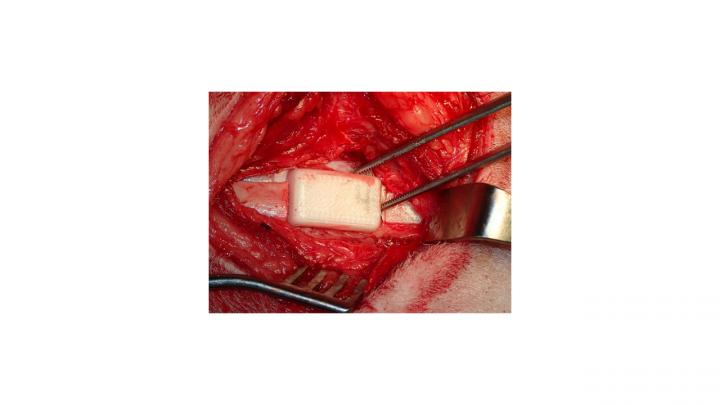

Using an ovine model, researchers reconstructed jawbones by filling 3D printed bioreactors with either autologous bone or synthetic graft and implanting the bioreactors for 9 weeks adjacent to sheep rib cages to grow and harvest bony tissue; the authors successfully repaired the jawbones of five out of six sheep and suggest that the bioreactors could aid efforts to repair human jawbone defects and loss.

Article #18-19246: "Biomaterials-aided mandibular reconstruction using in vivo bioreactors," by Alexander M. Tatara et al.